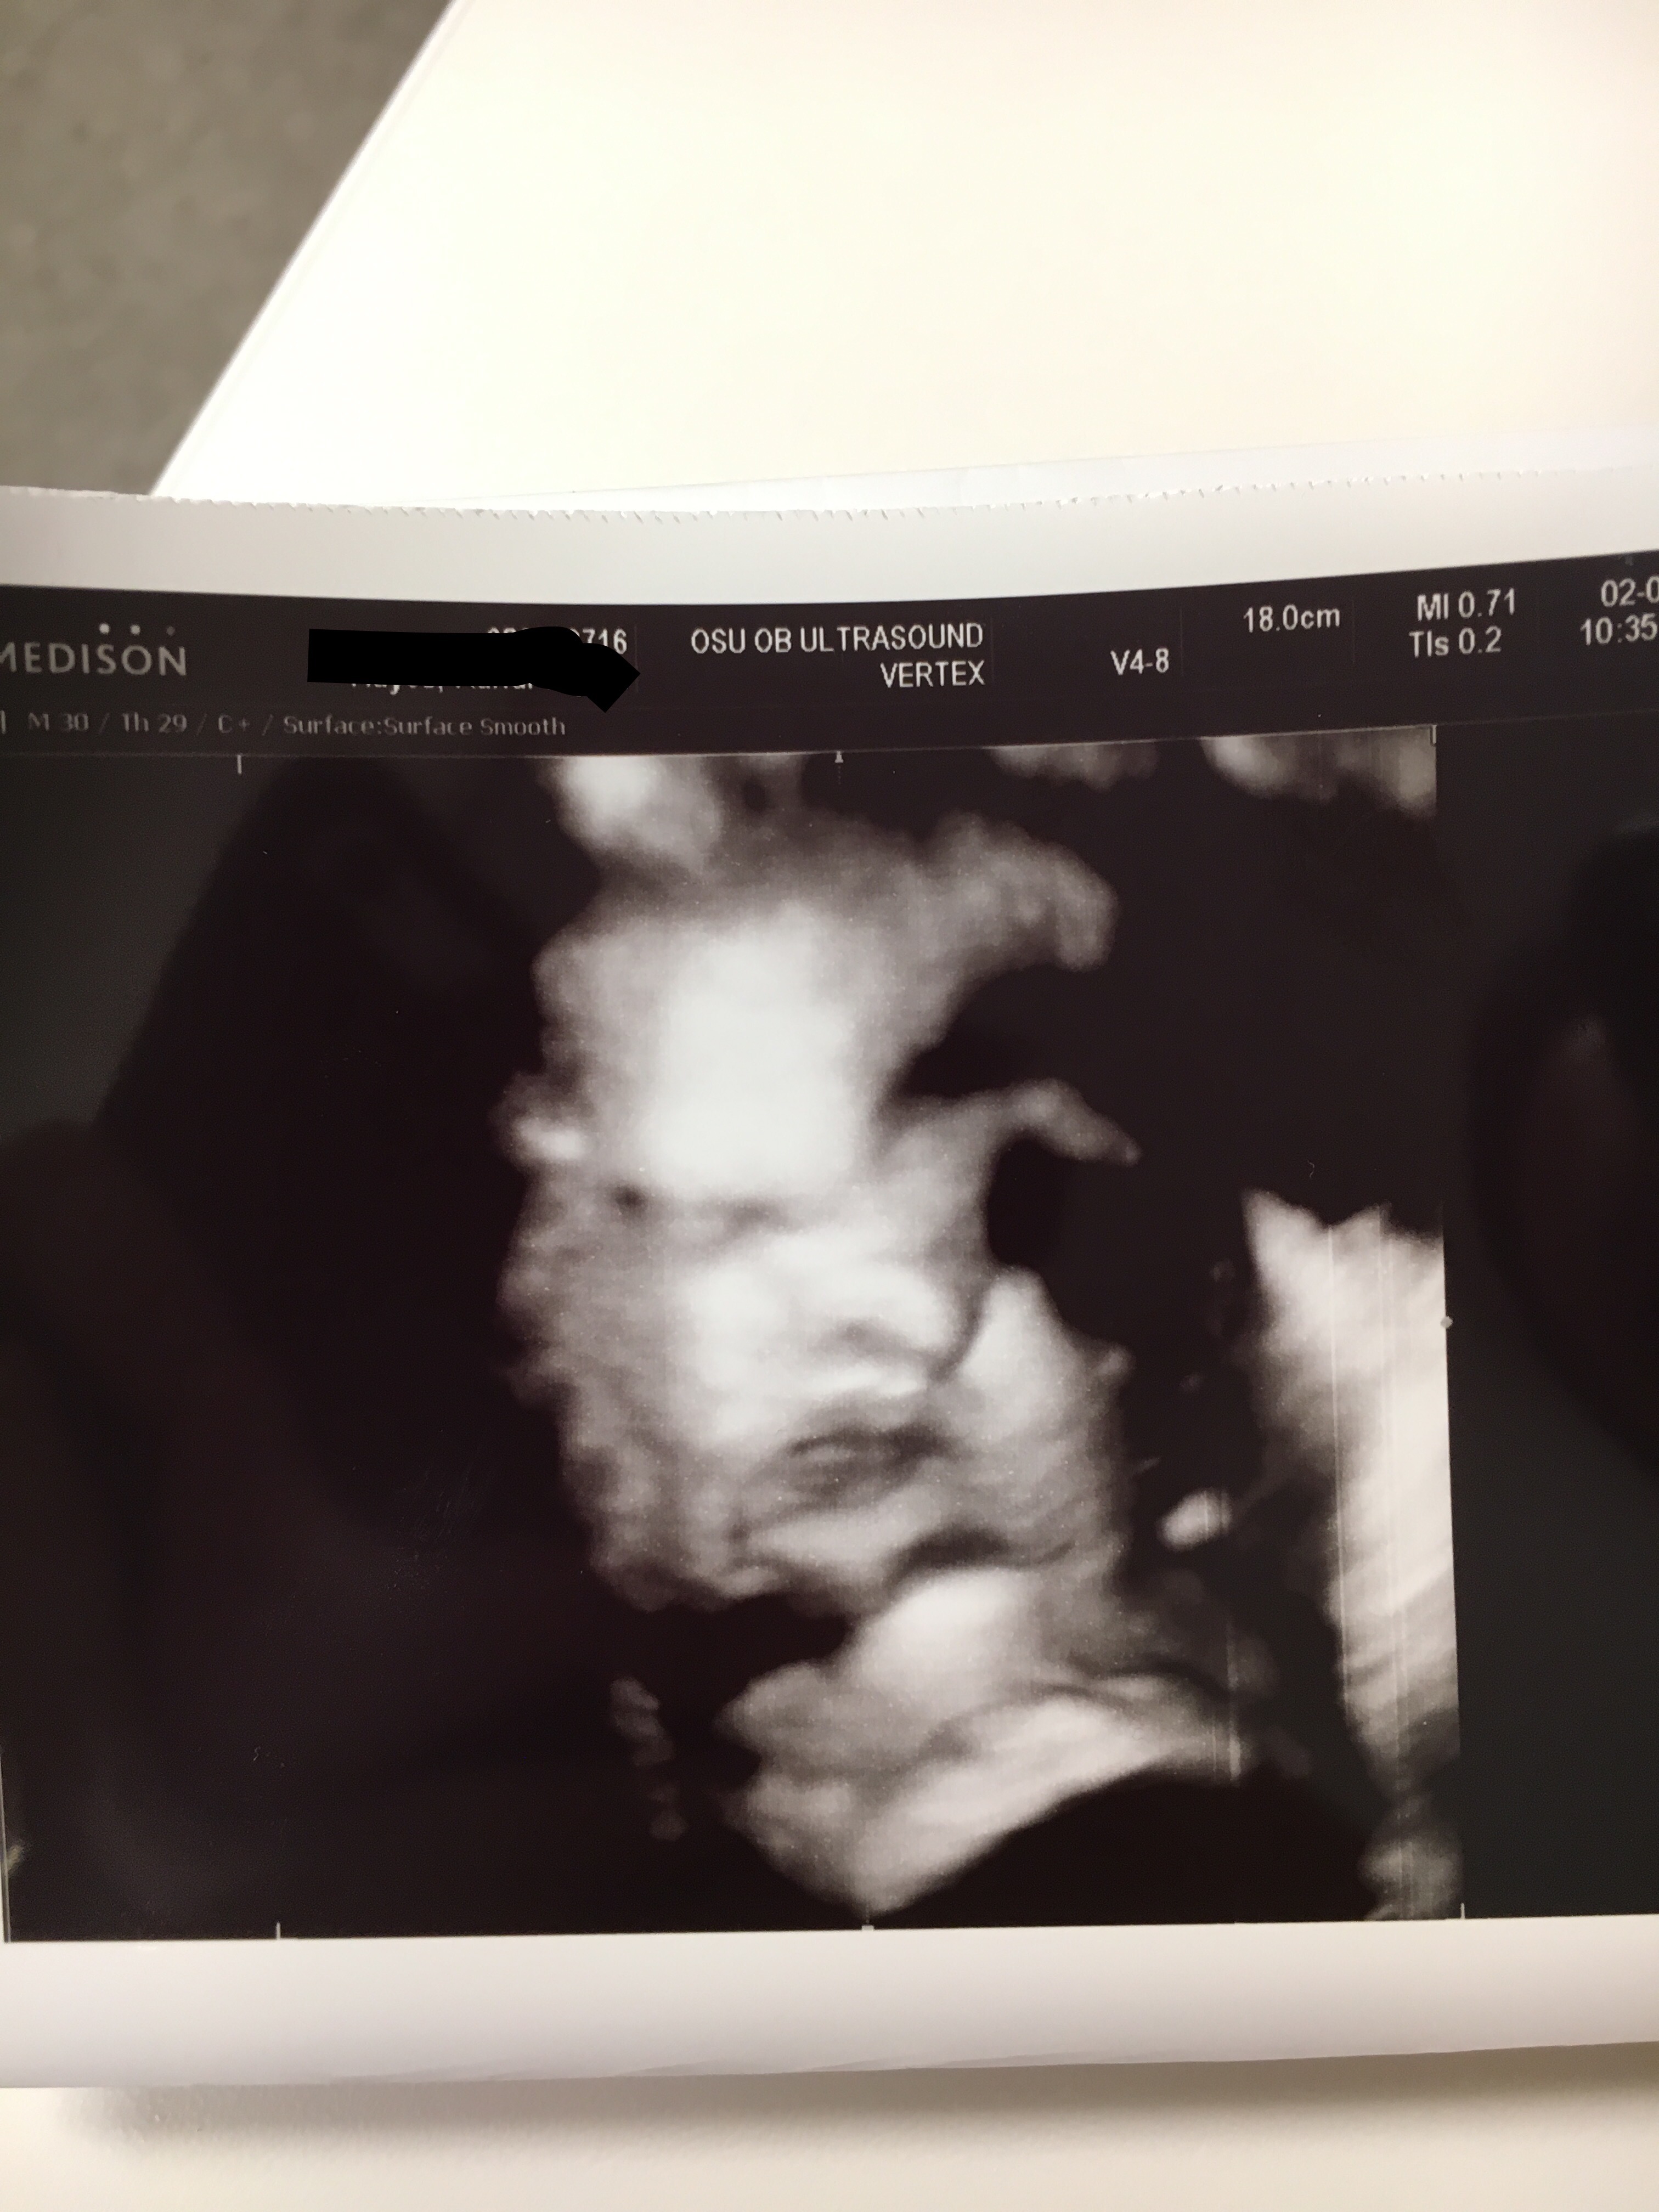

Now for some pictures.

The white lines next to the word “hair” is her hair! Apparently she has a bunch!